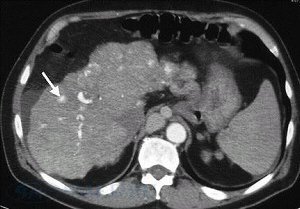

• Компьютерная томография брюшной полости.

Этот метод позволяет визуализировать контуры и структуру внутренних органов на серийных снимках-срезах.

Узлы регенерации паренхимы печени у пациента с циррозом.

На снимке визуализируется увеличение левой (L) и хвостатой (С) долей печени; фокальный фиброз и атрофические изменения в правой доле (указаны открытой стрелкой). Развитие коллатералей (указаны белыми стрелками).